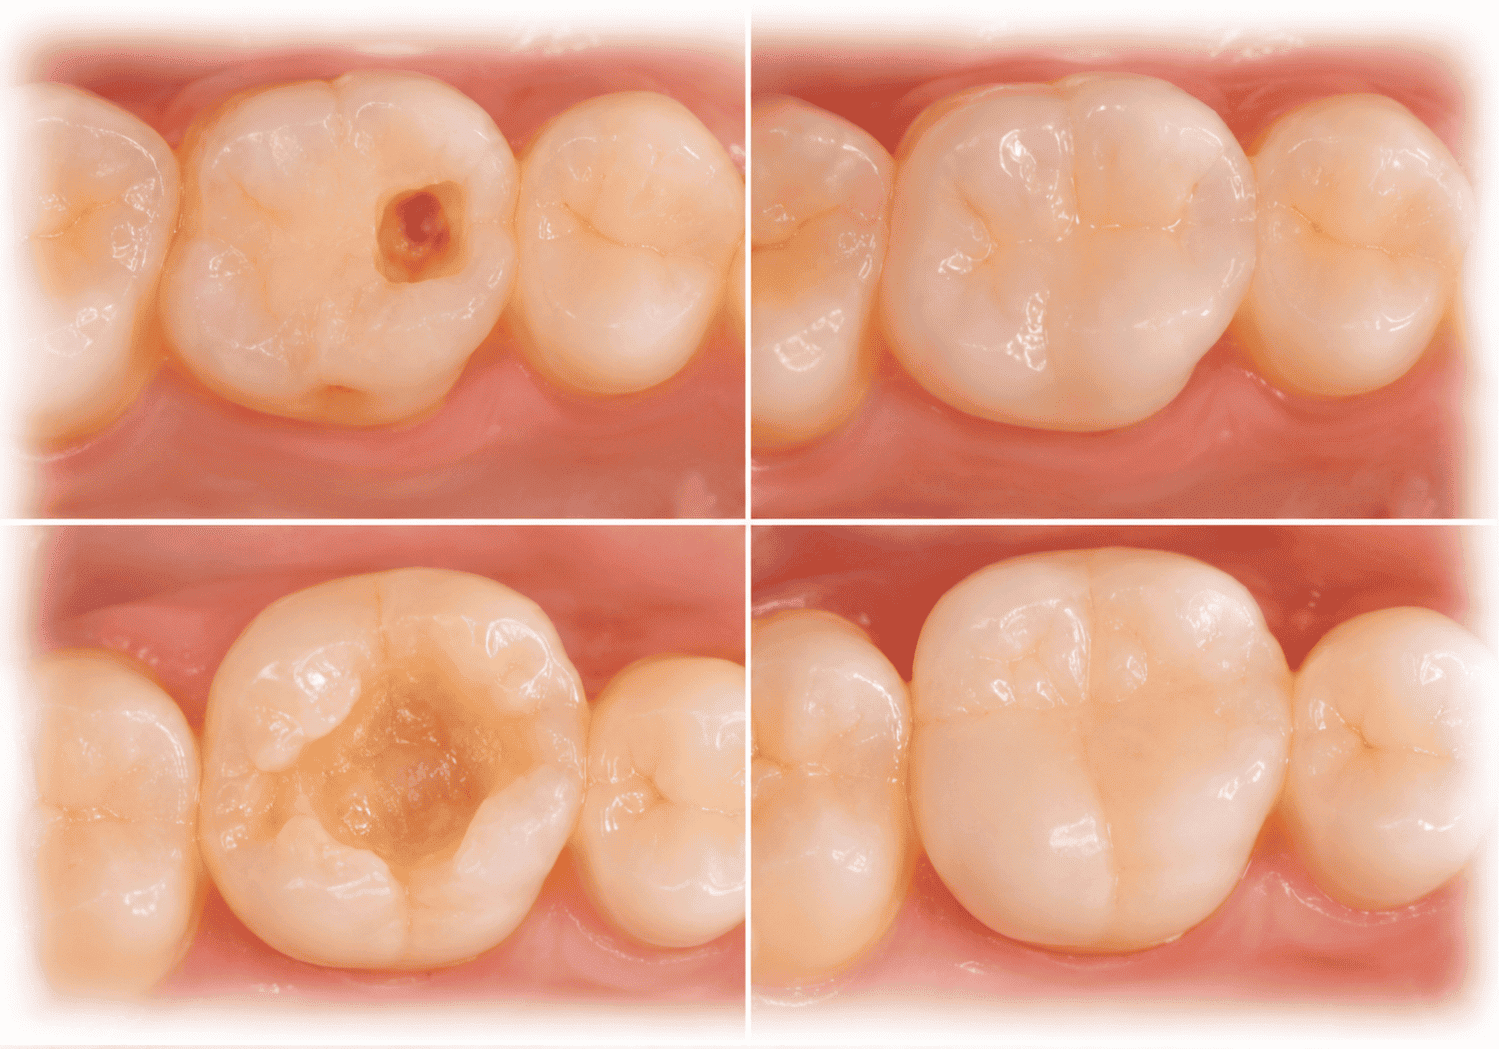

দাঁতের ফিলিং ও পুনর্গঠন (Restorations: Composite, GIC)